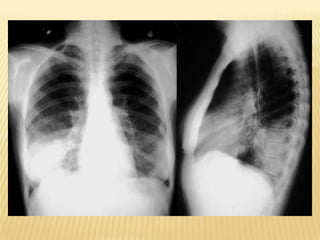

Assessment and diagnosisChest radiographSputum Gram stain and cultureDiagnostic bronchoscopyCBC with differential countChemistry panelBlood culturesABG

Assessment and diagnosisChestradiographSputum Gram stain and cultureDiagnostic bronchoscopyCBC with differential countChemistry panelBlood culturesABG